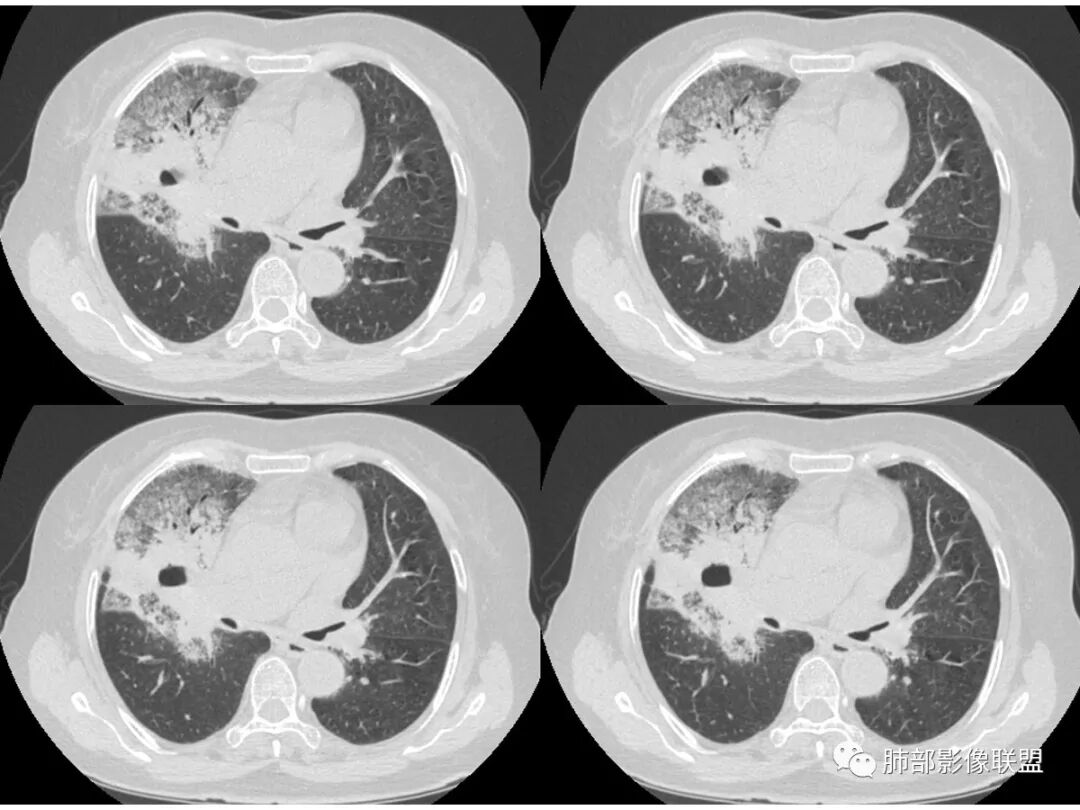

胸CT:右肺上叶实变内可见支气管充气征,近端支气管狭窄,远端扩张,周围可见毛玻璃影,右肺中叶支气管闭塞,并可见气道壁钙化,右肺中叶体积缩小,实变内可见空洞,并可见气液平面,空洞周围可见毛玻璃样影,右肺下叶支气管开口狭窄,右肺门淋巴结肿大。纵隔窗可见病灶与壁层胸膜间隙增宽,考虑良性病变-----感染性病变------TB?

老年女性,右肺中上叶病灶,血象不高,血沉高,TB dna阴性,上叶尖端病灶,紧贴胸膜,边界似清非清,中间可见实变,内见枯树枝征,首先考虑粘液腺癌可能性大。患者右肺中叶见空洞、气液平,病灶没多发空洞,可见气液平,考虑合并TB感染。

病史老年女,白痰;影像实变,ggo多数边界清,病灶下缘部分不清,枯树枝,支气管近端阻塞、僵硬,病灶跨叶;病灶内空洞,有液平;间质增厚有结节感;肺炎型肺癌大于干酪性肺炎。

右中叶支气管完全阻塞伴厚壁空洞,右上叶支气管不全阻塞伴大片GGN,右下部分GGN考虑腺鳞癌,结核待排。

老年女性,慢性病程,咳嗽伴白色粘液痰,无发热腹痛,糖尿病,白细胞及C反应蛋白不高,血沉快,铁蛋白高。胸部CT,右肺上叶大片状实变伴磨玻璃密度影,边界不清,边缘局部膨隆,叶裂弧形下坠,实变影宽基底与胸膜相贴;右肺下叶前基底段见类似病灶;右肺中叶不张并空洞形成,空洞内见气液平面;综合考虑右肺上叶及下叶肺炎型肺癌,右肺中叶结核。

老年女性,病史1月,右肺上中叶大片状影,跨叶,上叶为主,磨玻璃为主,边界模糊,部分实变,内见空洞影和液气平面,壁光滑,支气管开口狭窄,局部有扩张,右肺门淋巴结钙化,首先考虑感染性病变,结核可能,鉴别粘液腺癌。

老年女性,亚急性起病,右肺上中叶大片状影,跨叶,上叶为主,磨玻璃为主,边界模糊,部分实变,内见空洞影和液气平面,壁光滑,洞内可见结节形成,局部有扩张,首先考虑感染性病变,结核可能;洞内可见结节样病灶,鉴别合并曲霉、肿瘤。

这里是中叶的不张和空洞,有钙化,结核确实也不能排除

主病灶应该是粘腺腺癌,右中叶不张?,内空洞,壁光滑,考虑感染

1.王老师的病理说明粘液腺癌的破坏力弱,对血管和支气管破坏少,所以理论上空洞少,这个空洞很明确。

2.南大理论:粘液腺癌起源于外周,所以主体病灶位于胸膜下多见,这个病人主体病灶位于中心,外周磨玻璃为主,部分磨玻璃模糊

中叶的体积缩小,也不是粘液腺癌能完全解释,